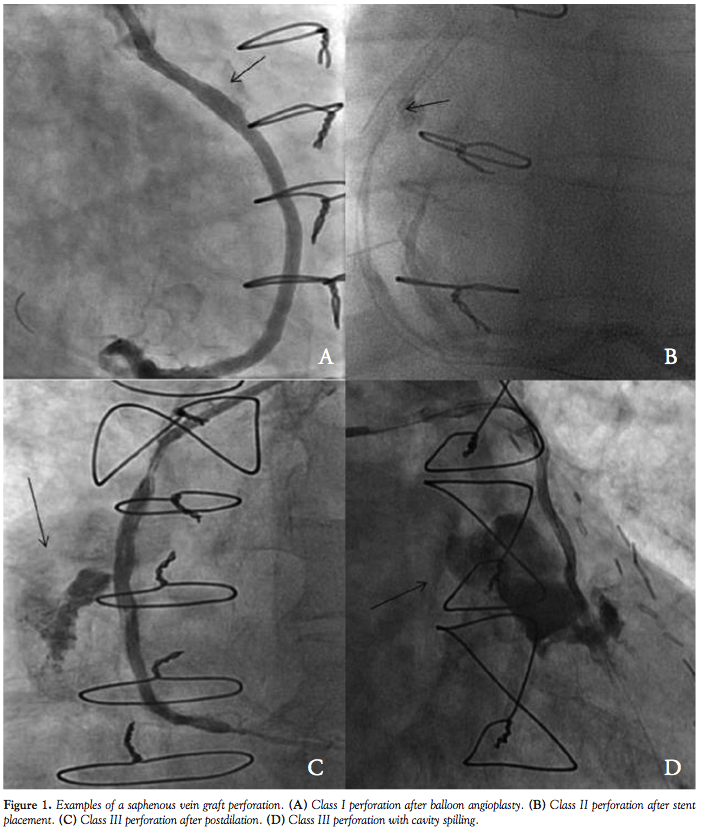

We identified all patients who developed SVG perforation during SVG PCI between November 2005 and November 2011 at the Montreal Heart Institute in Montreal Canada and at William Beaumont Hospital in Royal Oak, Michigan. The severity of perforation was classified according to the Ellis classification,6 as follows:

Class I: A crater extending outside the lumen only in the absence of linear staining angiographically suggestive of dissection.

Class II: Pericardial or myocardial blush without a ≥1 mm exit hole.

Class III: Frank streaming of contrast through a ≥1 mm exit hole.

Class III-cavity spilling: Perforation into an anatomic cavity chamber, such as the coronary sinus, the right ventricle, etc.

Patients. During the study period, twelve SVG PCIs were complicated by SVG perforation (Figure 1). The clinical characteristics of the patients who developed SVG perforation are shown in Table 1. Most patients (75%) were men presenting with an acute coronary syndrome and mean age was 73 ± 11 years. Mean SVG age was 12 ± 8 years. Most SVG perforations occurred in old SVGs (≥9 years post coronary bypass graft surgery); however, in 3 patients that target SVG was ≤1 year old. Patients who had SVG perforation had extensive native coronary artery and SVG atherosclerosis (Table 2). All except 1 patient had patent left internal mammary grafts to the left anterior descending artery.

Procedural outcomes. The location of the target SVG lesion was in the SVG body (n = 6), aortic anastomosis (n = 3), or distal anastomosis (n = 3). Most perforations occurred after stent implantation (n = 5) or after stent postdilation (n = 3). In the remaining 4 cases, perforation was caused by lesion predilation, use of an aspiration catheter, use of intravascular ultrasonography, and use of a coronary guidewire. The perforation was Ellis class I in 1 patient, II in 3 patients, III in 4 patients, and III with cavity spilling in 3 patients. The perforation spontaneously sealed without requiring further treatment in 3 patients with class I or II perforation (Table 3). In the remaining 9 patients, the perforation was